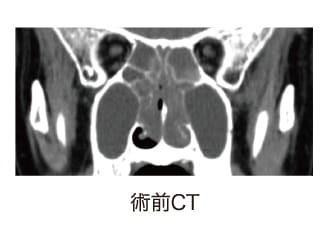

○内視鏡下手術による好酸球性副鼻腔炎の治療術前CTでみられた副鼻腔の炎症(灰色)が、術後CTでは正常(黒色)になっています